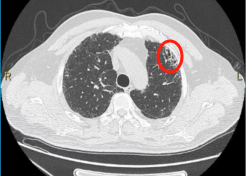

▲2019年胸部CT显示,少许间质性肺炎

(画圈处)改变

▲2023年胸部CT显示,双肺间质性肺炎

(画圈处)病变较前增多、进展